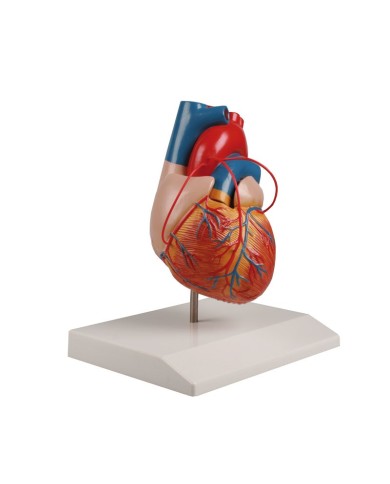

Modello di cuore di alta qualità scomponibile in 5 parti

Modello di cuore di alta qualità scomponibile in 5 parti

Modello anatomico di cuore, ingrandito 2 volte, su cavalletto